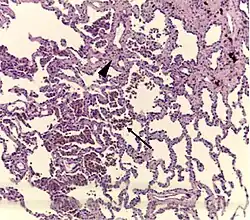

Histopathology of respiratory bronchiolitis: Smoker's macrophages (arrow); mild interstitial lymphocytic infiltrate and mild fibrosis (arrowhead)[2]

A "smoker's macrophage", with yellow to light brown and finely granular cytoplasmic pigment.